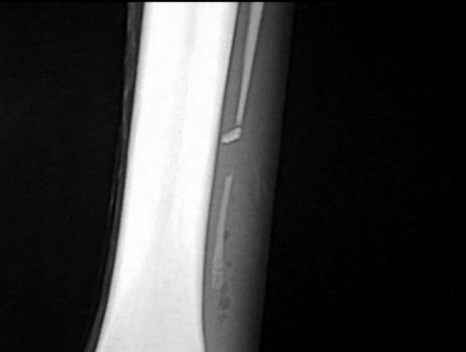

Griffelbeinfraktur